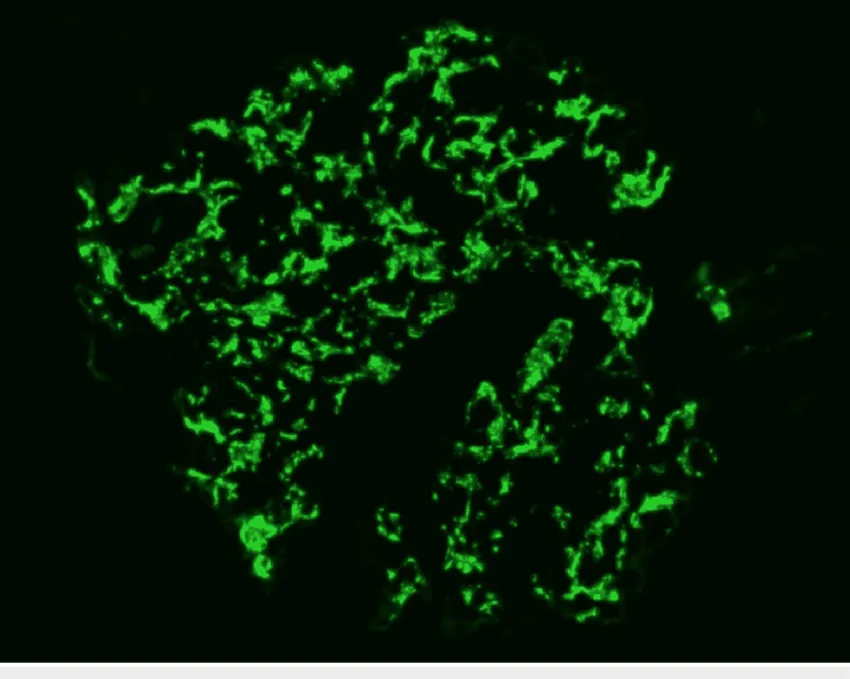

Paciente dislipidêmica, 47 anos, tomando suplemento "natural" para colesterol. Nenhuma queixa renal — até a creatinina chegar em 4.26. O agente não era uma droga controlada. Era arroz vermelho fermentado. E o rim foi o alvo.